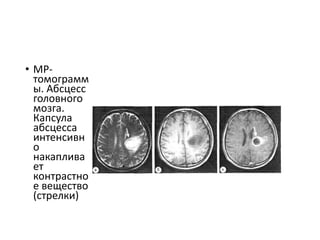

• MP-

томограмм

ы. Абсцесс

головного

мозга.

Капсула

абсцесса

интенсивн

о

накаплива

ет

контрастно

е вещество

(стрелки)